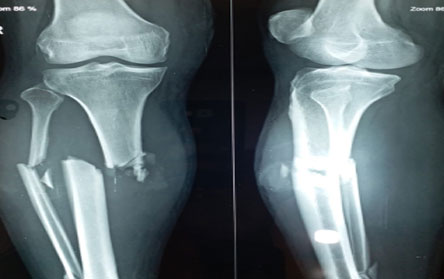

Trauma surgery:

Trauma surgery is a surgical specialty that utilizes both operative and non-operative management to treat traumatic injuries.

The Center of Orthopedics KUMAR ORTHO HOSPITAL ,Patna, offers the entire spectrum of modern orthopedic management, which is effective, patient - friendly & result oriented. In a nutshell, it is one stop treatment for all orthopedic ailments and fractures with emphasis on avoidance of complications, rapid mobilization, decreased period of confinement and an early return to normalcy.